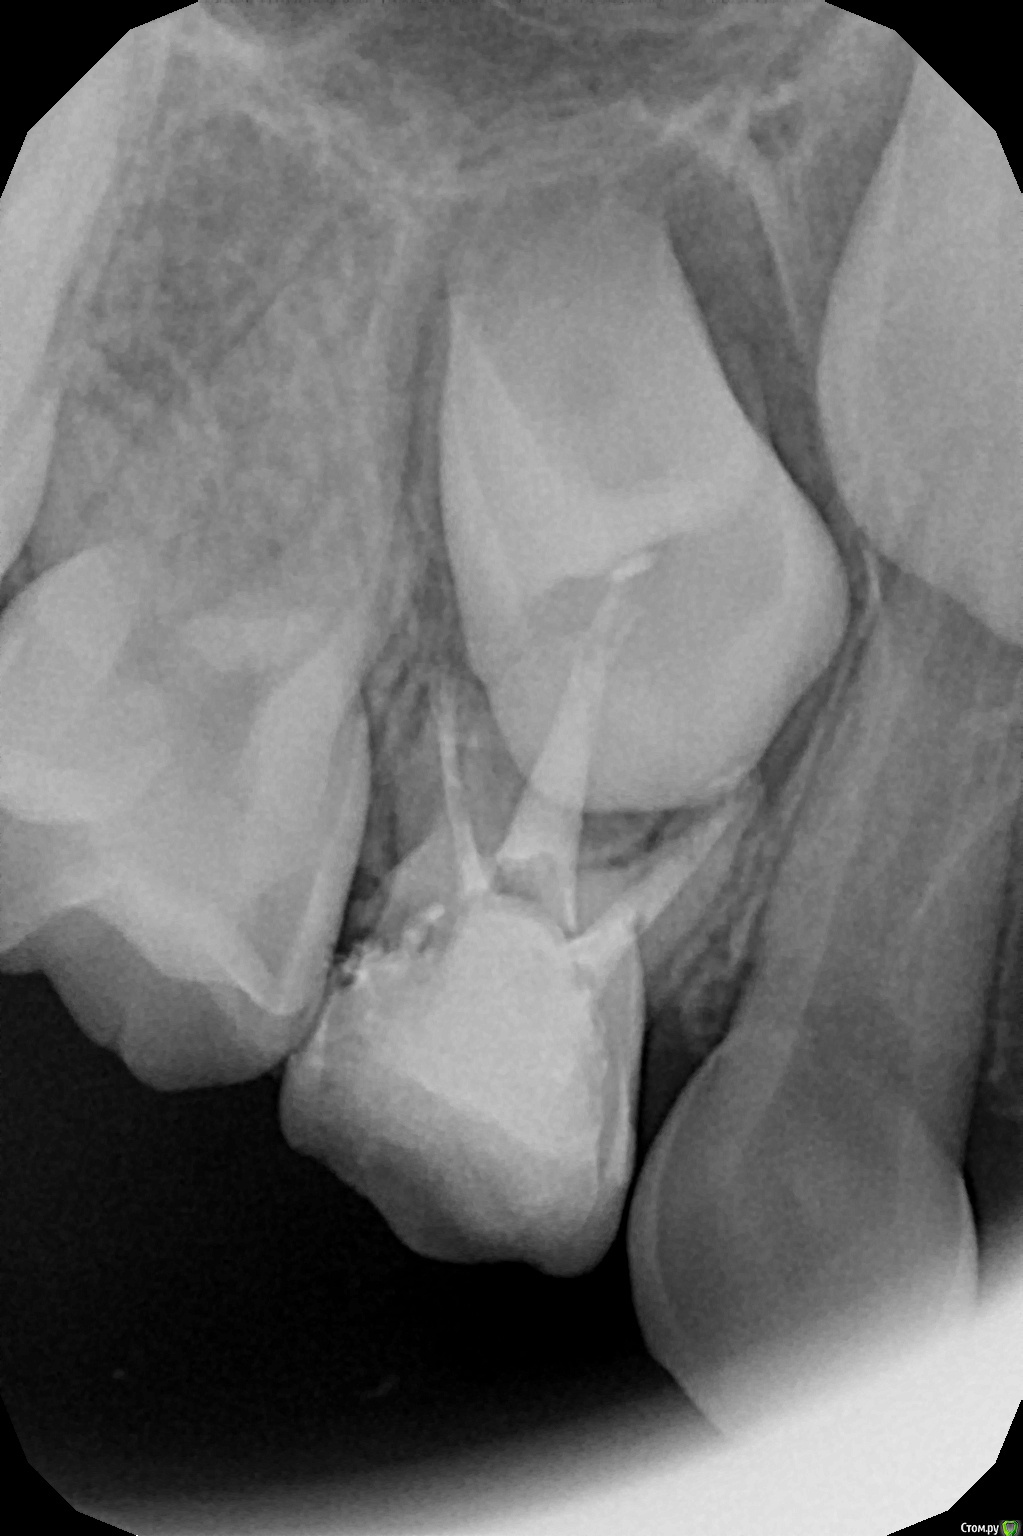

crown Опубликовано 11 августа, 2016 Поделиться Опубликовано 11 августа, 2016 Лечил 54, случайно обнаружил отсутствие зачатка 55. Ребенку 6 лет. Какова дальнейшая судьба 55? Будут ли рассасываться корни? Или так и будет стоять? Что вообще делать в такой ситуации? Если эндо и коронка, вариант? Надо другую сторону тоже глянуть на наличие зачатка. Ссылка на комментарий

Джима Опубликовано 11 августа, 2016 Поделиться Опубликовано 11 августа, 2016 если в нём эндо не делать, будет стоять до пенсии, скорее всего. коффер, кариес на контакте лечим нежно и асептично, и нехай стоит. 1 Ссылка на комментарий

red_butler Опубликовано 12 августа, 2016 Поделиться Опубликовано 12 августа, 2016 Какова дальнейшая судьба 55? будет сохранять место для последующей имплатации 1 Ссылка на комментарий

Kota Опубликовано 21 августа, 2016 Поделиться Опубликовано 21 августа, 2016 сейчас встречается часто. у нас по протоколу в 7 лет всем делать ОПТГ, по этому часто вижу на снимках. пока лечить, а потом что скажет ортодонт. либо сохранять место для имплантации, либо удалять со временем и 6,7 зубы закроют промежуток. все зависит от прикуса в целом. чаще всего такие зубы все таки резорбируются к 20 годам. Ссылка на комментарий